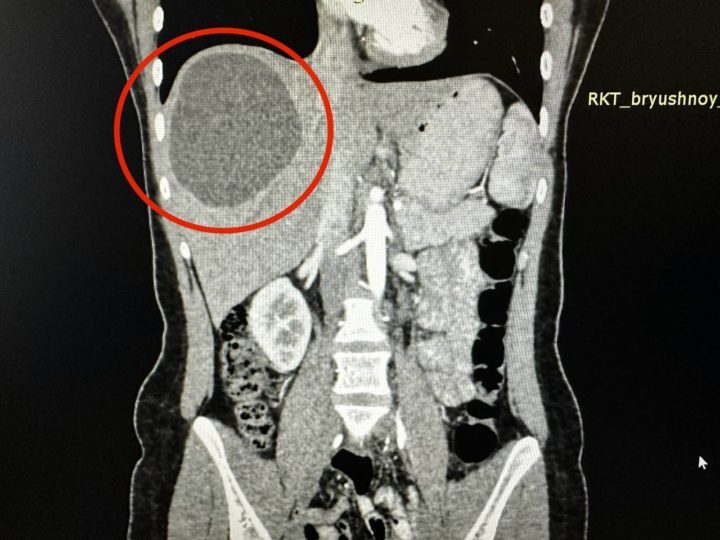

Несколько месяцев назад в Клиническую больницу Татарстана обратилась 19-летняя девушка с сильными болями в животе. Обследование показало, что в печени пациентки завелись паразиты, причем в огромном количестве: черви образовали кисту размером 15 на 20 сантиметров.

Накануне операции девушка прошла курс химиотерапии, чтобы убить паразитов, после чего хирурги больницы удалили эхинококк — так врачи называют этот ком червей. К сожалению, паразиты успели поразить часть органа, поэтому вместе с кистой пришлой удалить примерно треть печени.